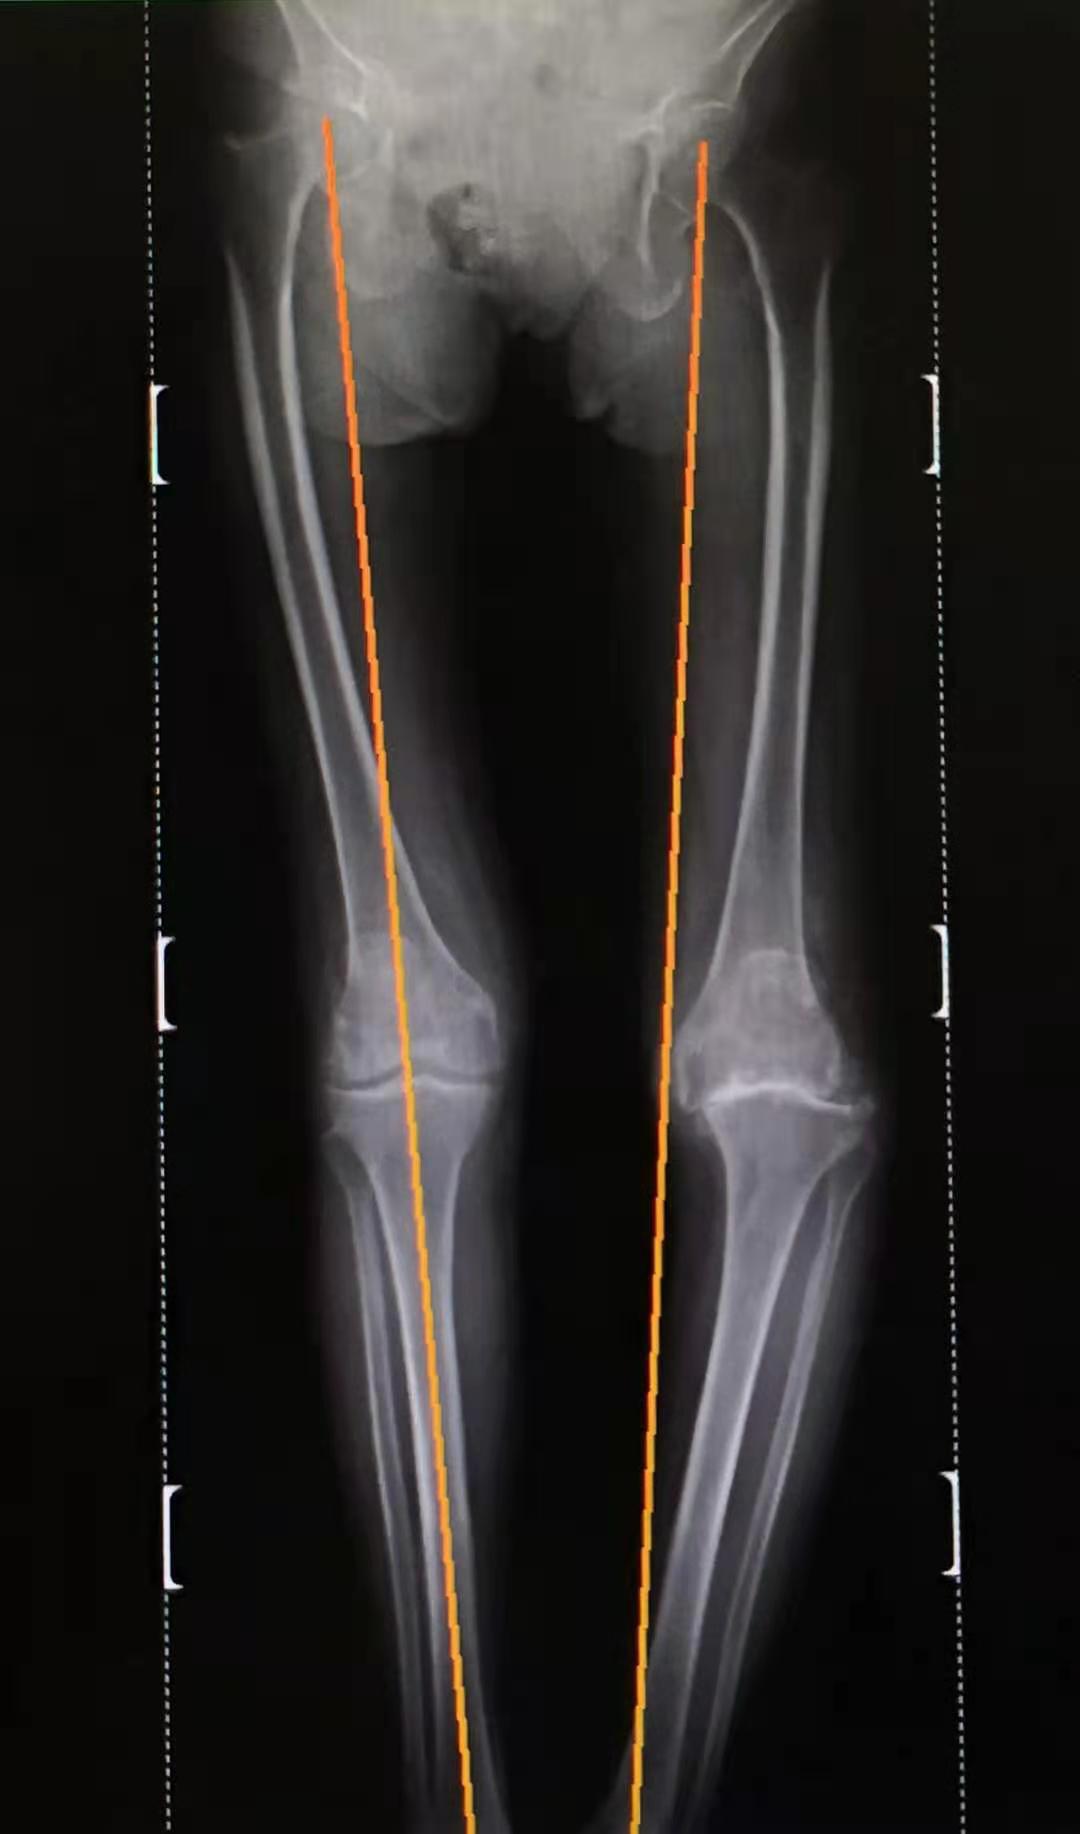

双下肢负重力线显示左膝关节内翻程度

双下肢力线恢复到正常